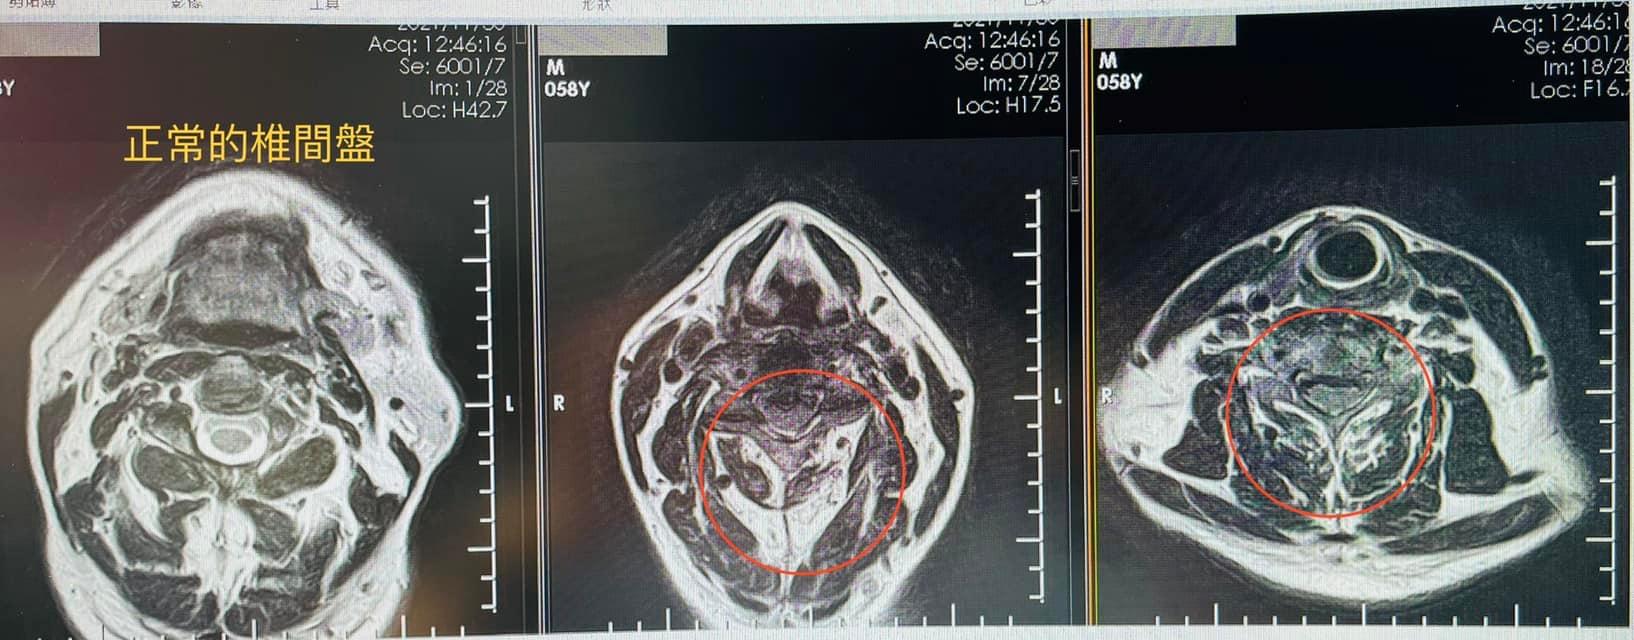

1.右側C3C4;C4C5;C5C6神經根型頸椎病

2.C3C4頸椎變型

事實上椎間盤在二十歲就發生退行性病變,大部分的人都是正常退化,但現代人手機電腦不離身,低頭族當久了,頸椎的生理曲線消失,變成頸椎過直,之後慢慢使得椎間盤的髓核突出,然後開始刺激與壓迫神經根,進一步產生周圍軟組織水腫發炎,最後產生纖維組織嚴重沾黏跟微循環障礙